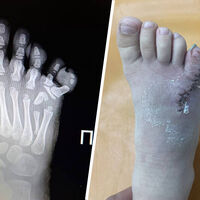

Врачи прооперировали четырехлетнюю россиянку с шестью пальцами

В Липецкой области врачи удалили четырехлетней девочке шестой палец на ноге

Врачи Ельцкой детской больницы прооперировали ребенка с полидактилией — врожденной особенностью, когда у человека есть лишние пальцы на ногах или руках. Об этом сообщили в пресс-службе администрации Липецкой области.

Медики отметили, что из-за своей особенности четырехлетняя пациентка жаловалась на боль в ступне. Также ребенку было сложно подобрать подходящую обувь.

Операцию девочке провел травматолог-ортопед Махач Алиев.

Глава Липецкого Минздрава Анна Маркова, комментируя случай из медицинской практики, отметила, что раньше подобные операции проводились только врачами из федеральных центров.